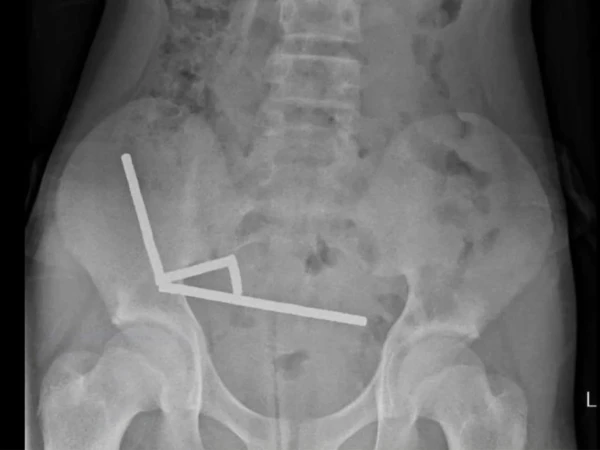

یہ گولیاں ایک آن لائن مارکیٹ پلیس (رپورٹ کے مطابق Temu) سے خریدی گئی تھیں۔ بچے کو چار دن تک معدے / پیٹ میں درد رہا، پھر اسپتال لایا گیا جہاں ایکس رے سے مقناطیسوں کی زنجیری شکلوں کا مشاہدہ ہوا جنہوں نے مختلف حصوں میں جمع ہو کر نقصان پہنچایا ہوا تھا۔

لڑکے کی سرجری کی گئی اور مقناطیسوں کے ساتھ ساتھ آنتوں کے اس حصے کو نکالنا پڑا جہاں ٹشوز شدید نقصان کا شکار ہوئے تھے۔

واضح رہے کہ جب بچے ایک سے زیادہ چھوٹے اور طاقتور مقناطیس نگلتے ہیں، تو وہ معدے یا آنتوں کے مختلف حصوں میں ایک دوسرے کے قریب آ کر “چپک” جاتے ہیں۔ یہ چپکنے والا عمل ٹشوز کے درمیان دباؤ پیدا کرتا ہے، خون کا بہاؤ متاثر ہو سکتا ہے، ٹشوز مردہ پڑ سکتے ہیں اور ردّعمل کے ساتھ بندش یا سوراخ بھی ہو سکتا ہے۔